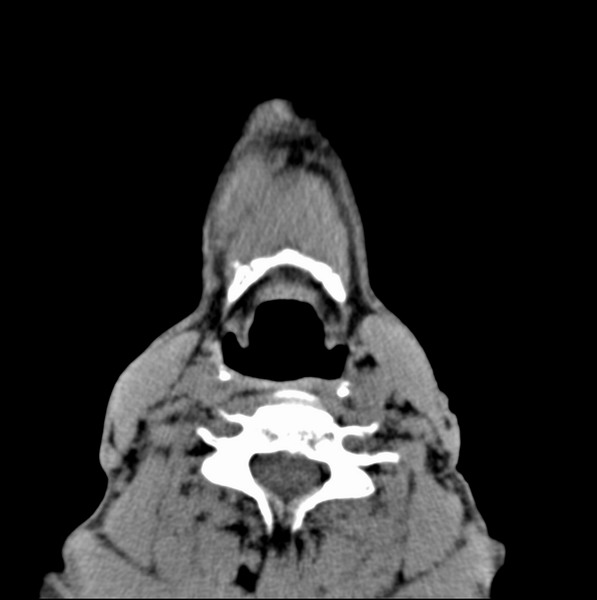

男、60、舌根肿物。

舌垂直肌和横肌影处肿块影,边缘不规则,咽腭扁桃体及舌下间隙脂肪影消失,病变侵及口咽。

考虑-----舌根癌

舌跟软组织肿块,较大有坏死,钙化。结合年龄一般是恶性肿瘤。

舌根部较大软组织肿块,其内见坏死低密度区及钙化影;考虑舌根癌可能。